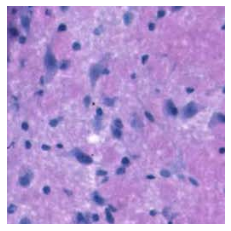

S1.1 Histology

To analyse tissue samples, pathologists take slices of tissue around 5m thick to be analysed under a microscope. To make it easier to identify different structures, the slide is typically stained with chemicals that bind tightly to different components of the sample, dying them different colours. By far the most common staining method used in histopathology is haematoxylin and eosin (H&E) staining. Haematoxylin stains components that are rich in nucleic acids, such as nuclei and ribosomes, while Eosin stains common protein structures pink, such as connective tissue, collagen, and the cytoplasm [54].

Immunohistochemistry is an ancilliary staining technique often used in medical diagnosis, which works by using an antibody to target specific proteins in tissue. Secondary chemical processes are coupled to the antibody to produce a colour, making it much easier to identify their presence and location within tissue. There are many different antibodies used which each target a specific protein or protein type. Common examples of antibody targets include cytokeratins, which are found in epithelial cells, CD3, CD4, and CD20, which are found in various types of immune cells, and smooth muscle actin (SMA), which is found in myofibroblasts [55].

Typically these stains are highly informative about one particular protein of instance, but lack the generality of H&E staining. Consequently, they are primarily used as secondary sources of information to assist with research or diagnosis.